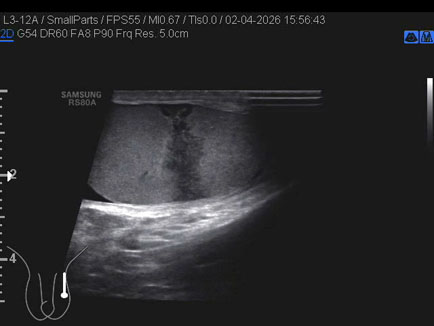

Data inserimento: 03/04/2026

Ecografia del: 12/03/2026

Strumento: Esaote MyLab Eight

Sonda: Convex Multifrequenza 1-8 MHz

Età Paziente: F 66 anni

Motivazione dell'esame: follow up per angiomiolipoma renale destro

Commento all'esame: le immagini ed il video documentano al rene destro, in sede corticale polo inferiore, immagine iperecogena, a margini definiti, delle dimensioni di 25 x 23 mm, senza segni di vascolarizzazione, da ricondurre, come prima ipotesi, ad angiomiolipoma.

Conclusioni: angiomiolipoma del rene destro (angiomyolipoma of the right kidney).

In collaborazione: Dr.ssa Marica Manfredi - Ancona, Dr. Ilir Qose - Ancona

Presentazione: Dr. Massimo Dolciotti - Ancona

Elaborazione digitale: Andrea Dini - Ancona